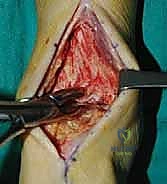

1. الوضعية والشق الجراحي (Positioning and Incision)

يستلقي المريض على ظهره (Supine position). يتم استخدام عاصبة (Tourniquet) حول الفخذ لتقليل النزيف وتوفير رؤية واضحة. يقوم الدكتور هطيف بإجراء شق طولي أمامي فوق مفصل الكاحل، عادة بين وتر العضلة الظنبوبية الأمامية (Tibialis Anterior) ووتر العضلة الباسطة الطويلة لإصبع القدم